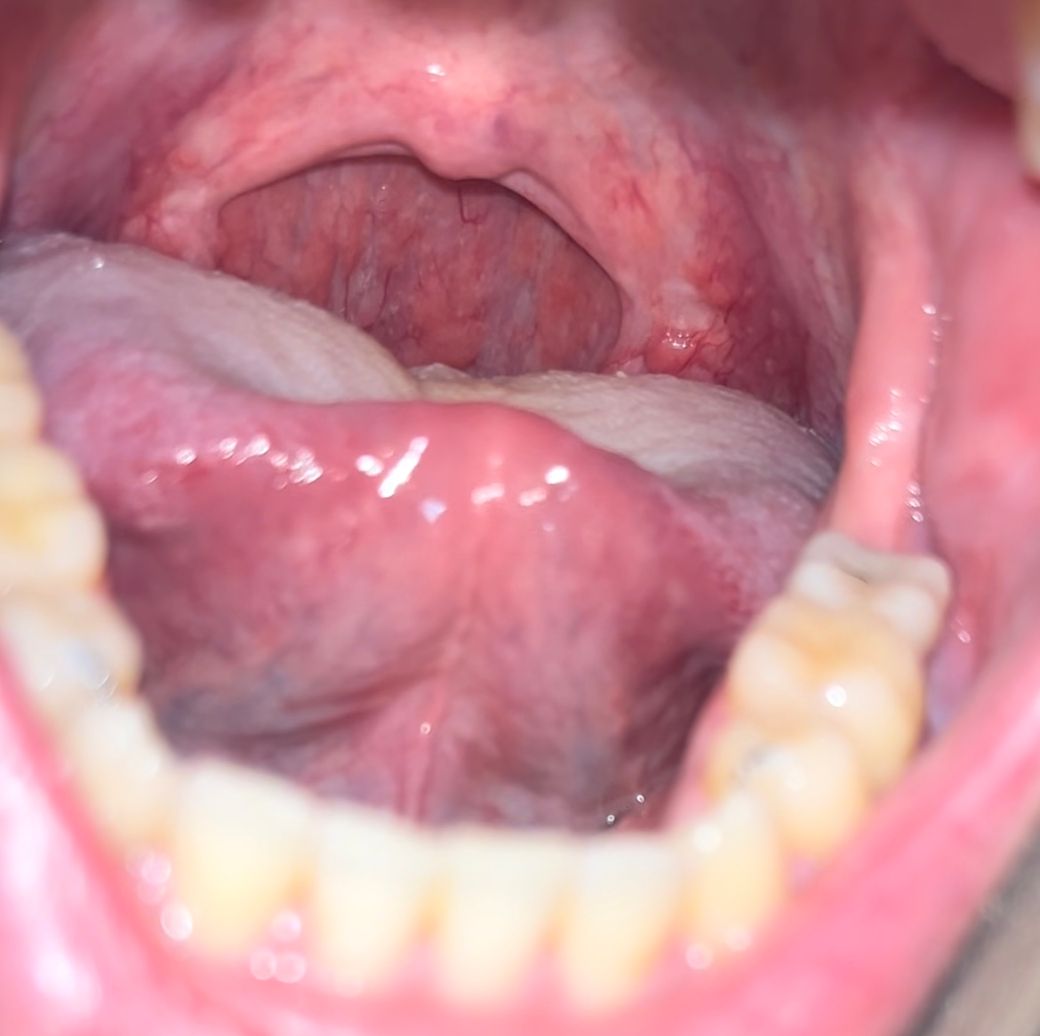

침에서 피가 섞인듯 나오고있습니다.

3주전부터 침을 뱉을때 피랑섞여서 나옵니다

침삼킬때 목따가운것은 없고

아침에 일어나서는 더 심한 편 입니다

병원에서는 인후염이라하여 약을 먹었는데

계속 그대로 입니다. 기침은 하지않고

가래는 가끔 나오는데 피는 섞여있지 않고

침에서만 피색깔이 나옵니다.

혹시 폐암이나 다른 질병일 가능성이 있을까요?

• 1번 째 사진

기침하다가 점막이 손상되어 나오는 피와

폐에서 나오는 객혈은 차이가 있습니다.

일단 객혈은 아닌것으로 보이며 염증 치료를 열심히 받아보세요